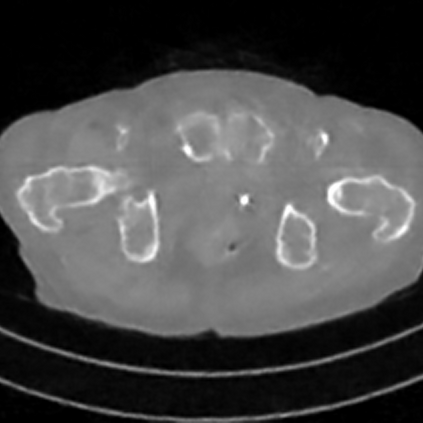

Sparse-view computed tomography (CT) -- using a small number of projections for tomographic reconstruction -- enables much lower radiation dose to patients and accelerated data acquisition. The reconstructed images, however, suffer from strong artifacts, greatly limiting their diagnostic value. Current trends for sparse-view CT turn to the raw data for better information recovery. The resultant dual-domain methods, nonetheless, suffer from secondary artifacts, especially in ultra-sparse view scenarios, and their generalization to other scanners/protocols is greatly limited. A crucial question arises: have the image post-processing methods reached the limit? Our answer is not yet. In this paper, we stick to image post-processing methods due to great flexibility and propose global representation (GloRe) distillation framework for sparse-view CT, termed GloReDi. First, we propose to learn GloRe with Fourier convolution, so each element in GloRe has an image-wide receptive field. Second, unlike methods that only use the full-view images for supervision, we propose to distill GloRe from intermediate-view reconstructed images that are readily available but not explored in previous literature. The success of GloRe distillation is attributed to two key components: representation directional distillation to align the GloRe directions, and band-pass-specific contrastive distillation to gain clinically important details. Extensive experiments demonstrate the superiority of the proposed GloReDi over the state-of-the-art methods, including dual-domain ones. The source code is available at https://github.com/longzilicart/GloReDi.